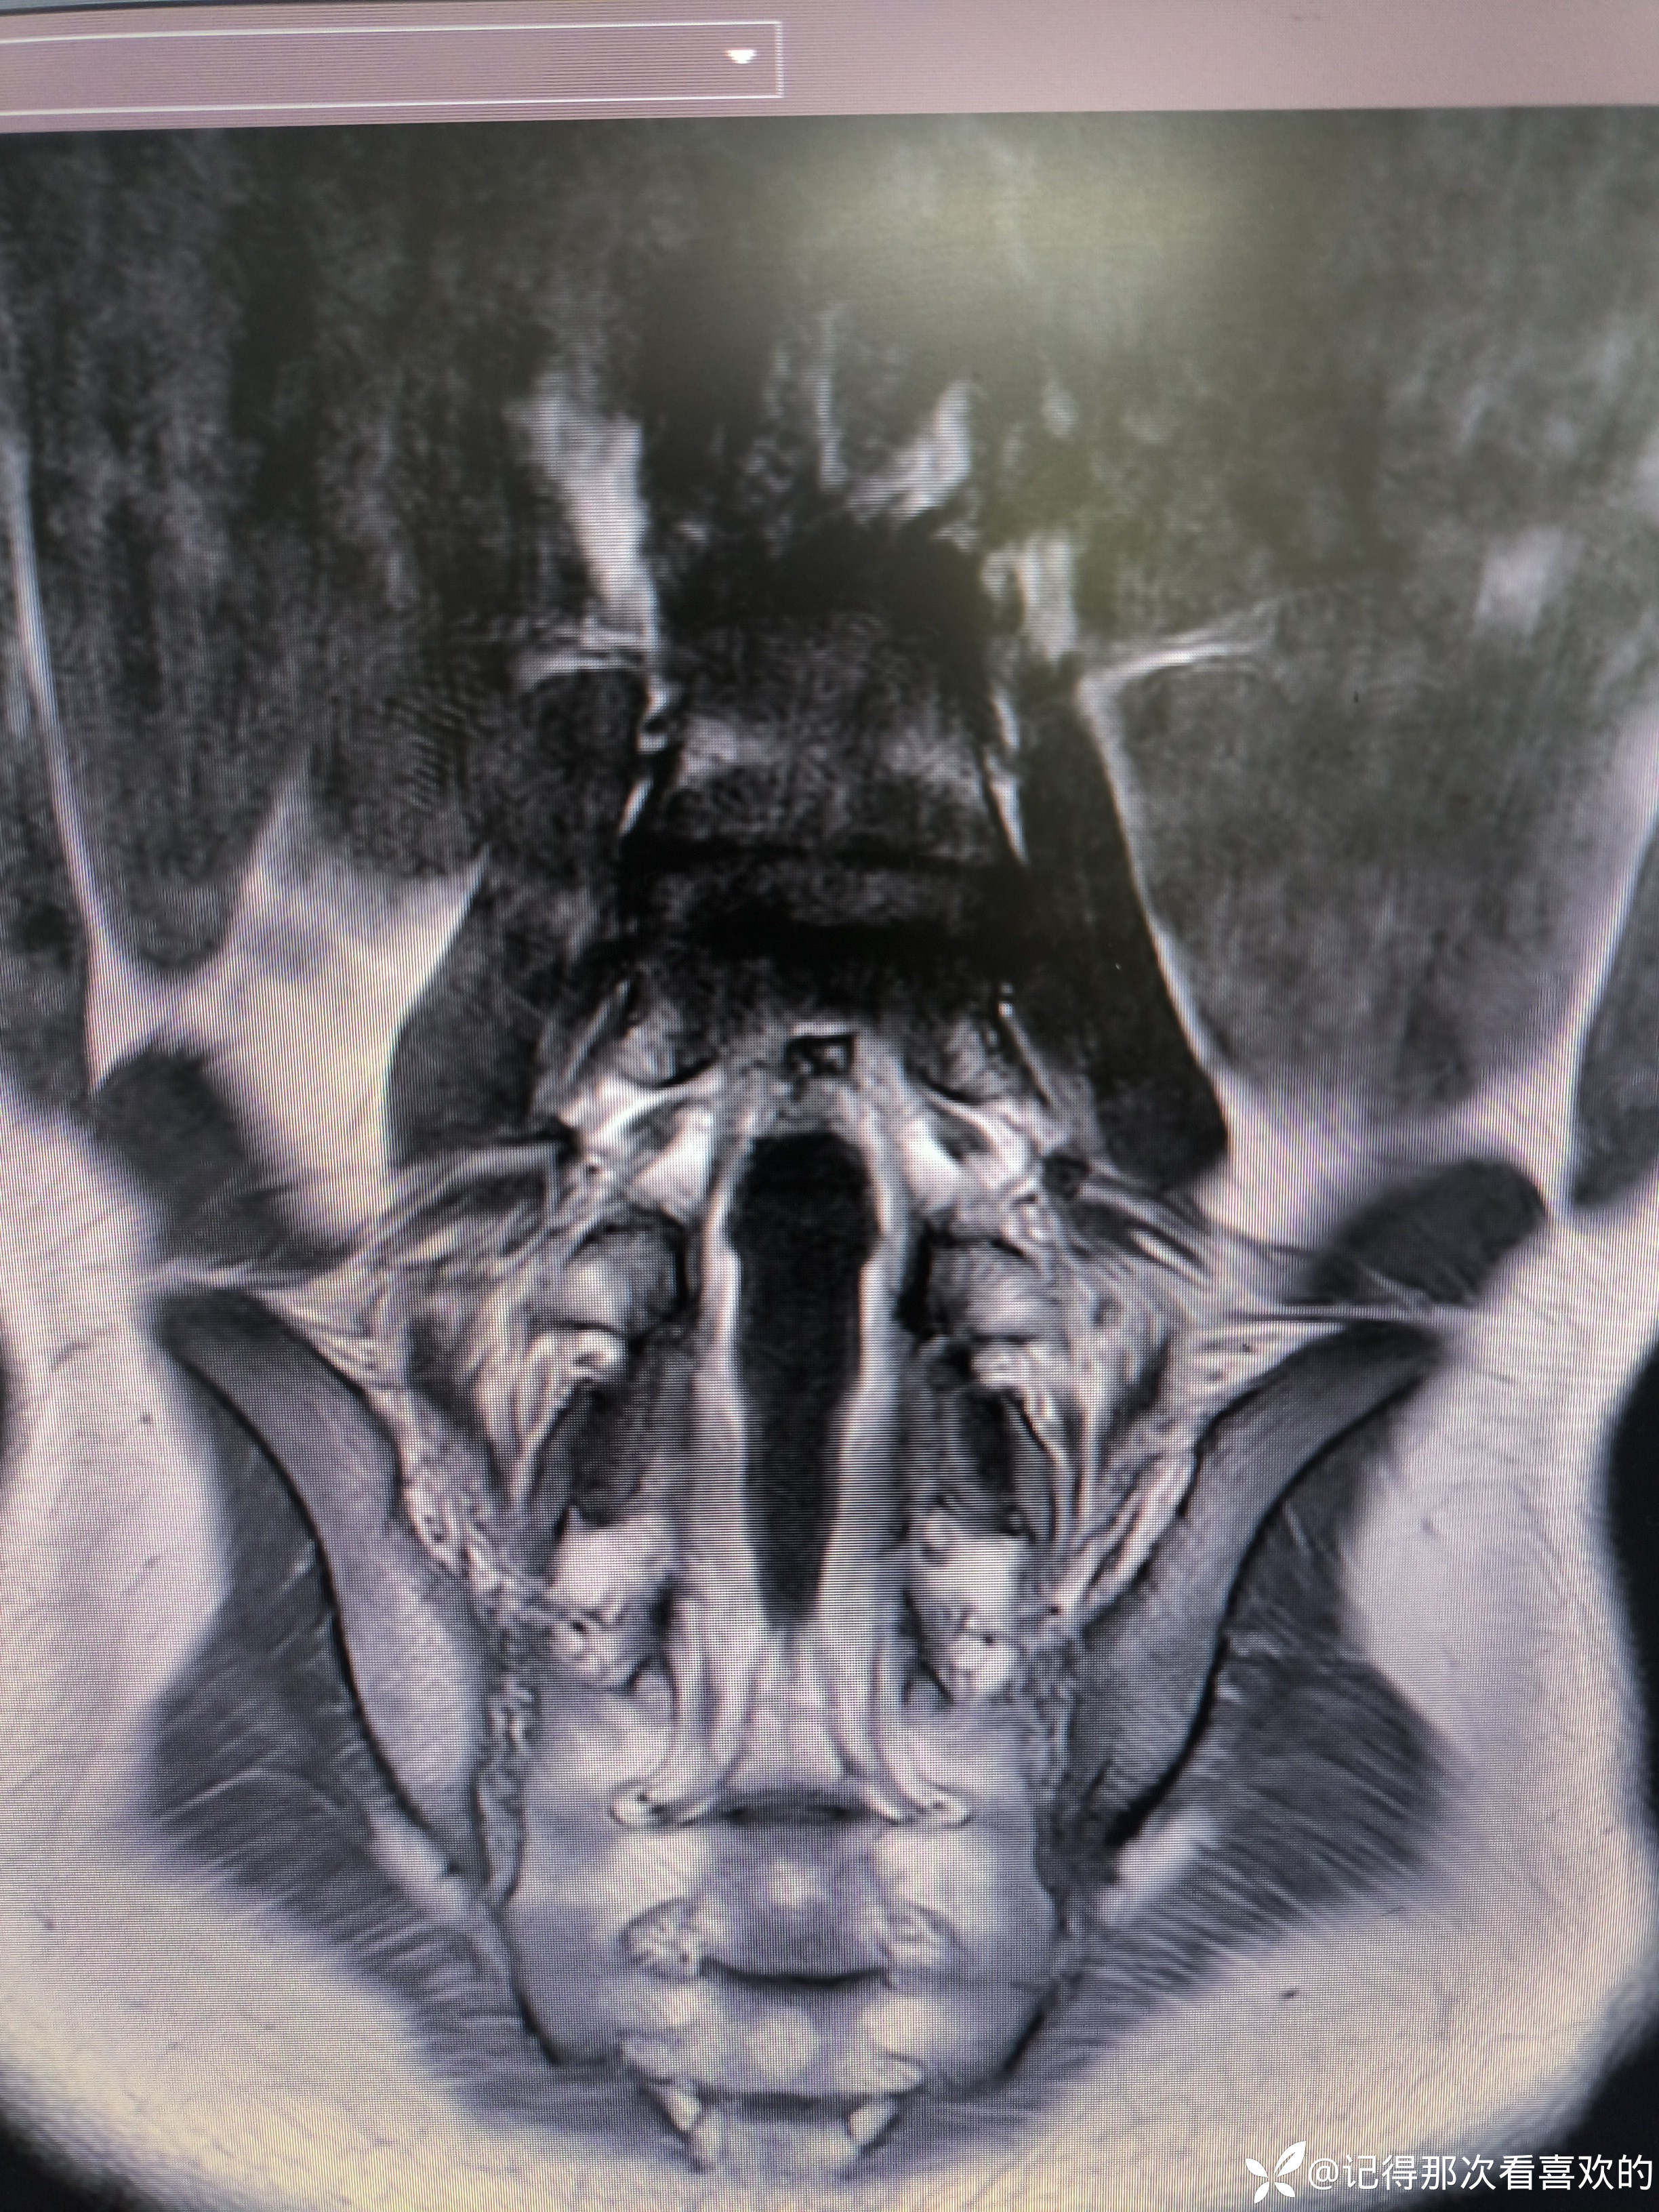

病例特点:患者钟某 男,14岁,以"髋、膝、足肿痛1年余,加重3日。"为主诉入院。现病史:缘于1年前无明显诱因出现左侧髋关节、双足跟、左踝关节、右足第一足趾关节肿胀、疼痛, 疼痛呈持续性,多于阴雨天、活动后症状加重,疼痛未向他处放射、转移,症状严重时行走困难。遂就诊于我科,查"HLA-B27(+)、CRP 70mg/L、骶髂MR:骶髂关节肿胀",诊断为"强直性脊柱炎",先后予皮下注射"司库其尤单抗150mg qw、阿达木单抗40mg q2w",上述症状较前好转,此后不规律用药,于半年前自行停用上述药物,未再规律随诊。3日前再发左膝、双肘关节肿痛,性质同前,程度较前加重,影响行走,伴有发热,体温最高达39℃,自行服用退烧药(具体不详)后体温较前下降,上述关节肿痛无明显改善。现为求进一步治疗,就诊我院,门诊拟"强直性脊柱炎"收住入院。体格检查:T36.6℃ P138次/分 R50次/分BP/120/68mmHg 专科情况:生命征平稳,神志清楚,双肺呼吸音清,未闻及干湿啰音,心律齐,各瓣膜听诊区未闻及杂音,全腹软,无压痛及反跳痛,未触及包块,双肘、左膝关节肿胀、压痛、触之皮温高。双下肢无浮肿,病理征未引出。

诊断依据:1.患者青年男性,以"髋、膝、足肿痛1年余,加重3日。"为主诉入院,疼痛多于阴雨天、活动后加重,病情严重时行走困难。2.查体:双时、左膝关节肿胀、压痛、触之皮温高。3.既往辅助检查提示HLA-B27阳性、影像学提示骶且关节炎。4.根据患者症状、体征及既往诊疗病史,目前考虑诊断强直性脊柱炎。5.余诊断根据既往病史可明确。

诊疗计划:1.入院予二级护理,监测血压、脉搏、呼吸。2.入院完善三大常规、凝血、生化、骶髂MR、彩超、CT、心电图等相关检查评估病情。3.治疗上暂予抗炎镇痛,辅以护胃治疗,待相关检查结果回报后进一步治疗,本次就诊拟行生物制剂治疗,予完善骨保护药物,传染病相关检查排除禁忌症,患者本次发病伴有发热达39℃,追问病史患者诉偶有干咳不适,目前已改善,予完善呼吸道病原学检查明确病情。4.患者Padua评分1分,属于发生VTE低危风险,实行VTE基本预防,动态评估Padua评分。5.已将目前病情及现有临床诊断以及存在疾病复杂性、个体的差异性、对治疗的反应不同、鉴于目前医学技术水平有限,和下一步相关诊疗详细充分告知患者家属,取得家属的理解并同意配合下一步诊疗及检查。6.NRS-2002评分3分,目前患者营养状态尚可,进食情况尚可,根据病情变化动态评估。